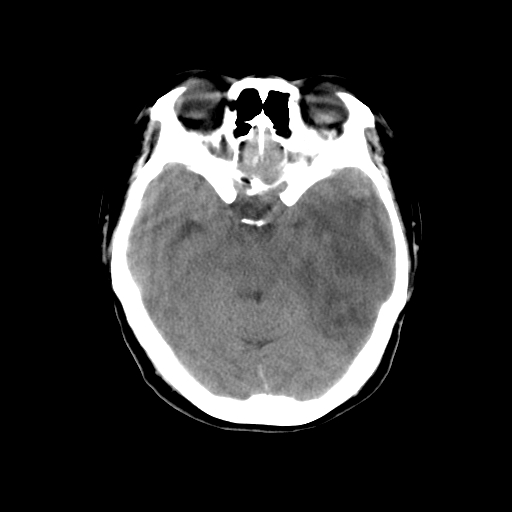

标题: CT14513:女性41岁,头部不适二月余,其它病史不详。请分析 [打印本页]

标题: CT14513:女性41岁,头部不适二月余,其它病史不详。请分析

考虑ii-iii级星形细胞瘤可能性大。

1.考虑:左侧颞顶叶星形细胞瘤。2.大脑镰下疝。